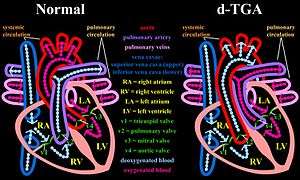

Transposition of the great vessels (TGV) is a group of congenital heart defects involving an abnormal spatial arrangement of any of the great vessels: superior and/or inferior venae cavae, pulmonary artery, pulmonary veins, and aorta. Congenital heart diseases involving only the primary arteries (pulmonary artery and aorta) belong to a sub-group called transposition of the great arteries.

Dextro-Transposition of the great arteries

In dextro-Transposition of the great arteries (dextro-TGA) deoxygenated blood from the right heart is pumped immediately through the aorta and circulated to the body and the heart itself, bypassing the lungs altogether, while the left heart pumps oxygenated blood continuously back into the lungs through the pulmonary artery. In effect, two separate "circular" (parallel) circulatory systems are created. It is called a cyanotic congenital heart defect (CHD) because the newborn infant turns blue from lack of oxygen.

Levo-Transposition of the great arteries is an acyanotic heart defect in which the primary arteries are transposed, with the aorta anterior and to the left of the pulmonary artery, and the morphological left and right ventricles with their corresponding atrioventricular valves are also transposed. The systemic and the pulmonary circulation are connected. Complications arise from the fact that the right ventricle, which is designed for pumping blood into the low pressure pulmonary circulation, is being tasked with pumping blood at a much higher pressure against the high resistance of the systemic circulation.

In many cases, TGV is accompanied by other heart defects, the most common type being intracardiac shunts such as atrial septal defect including patent foramen ovale, ventricular septal defect, and patent ductus arteriosus. Stenosis, or other defects, of valves and/or vessels may also be present.